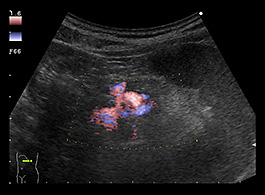

膵嚢胞は、膵臓上または膵臓内にある液体のポケットです。症状がほとんどないため、診断が難しい場合があります。これらは、別の問題の画像検査 ( CT スキャンなど) を実施するときに偶然発見されることがよくあります。

膵嚢胞の可能性が心配な場合は、医師に相談してください。病歴の検査に加えて、CT スキャン、MRI スキャン、超音波内視鏡などのさまざまな検査を実行できます。

検査後、医師は細胞が癌性かどうかを判断するために体液のサンプルを採取することがあります。膵炎が進行している場合は、嚢胞が再発する可能性があることに注意することも重要です。